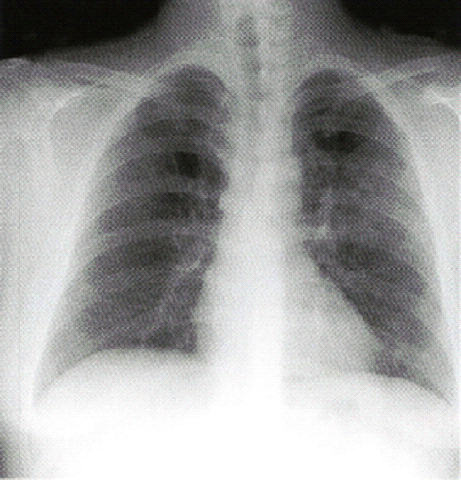

21歳の男性。

発熱と強い咳嗽とを主訴に来院。

生来健康であったが、1週前から出現した症状が近医での投薬にもかかわらず持続している。

喀痰は少ない。

既往歴に特記すべきことはないが、家族に同様の症状を示すものがいる。

意識は清明。

身長180cm、体重70kg。体温39.0℃。脈拍64/分、整。血圧128/68mmHg。

心雑音はない。左背部に軽度のcoarse cracklesを聴取する。

尿所見:蛋白(-)、糖(-)、潜血(-)。

血液所見:赤沈26mm/1時間、赤血球510万、Hb13.4g/dl、白血球8,900、血小板22万。

血清生化学所見:AST42IU/l、ALT35IU/l。CRP6.8mg/dl。

胸部エックス線写真と胸部単純CTを示す。

マイコプラズマ肺炎 マイコプラズマ肺炎CT

健康な成年に生じた発熱、強い咳嗽、喀痰は少ないことから、マイコプラズマ肺炎が疑われます。

治療を受けるも症状が持続という病歴から通常の細菌性肺炎よりも非定型肺炎が考えられ、 体温39.0℃にも関わらず脈拍は64/分と比較的徐脈であり、CRP6.8mg/dlと炎症所見を認めるが、 白血球はそれほど上昇していないこともマイコに矛盾しない所見です。

また、画像、特にCTでは気管支壁の肥厚がみられ、気管支病変が考えられます。

中枢側優位の所見で、小葉中心性の陰影かどうかははっきりしませんが、マイコで矛盾ない所見です。